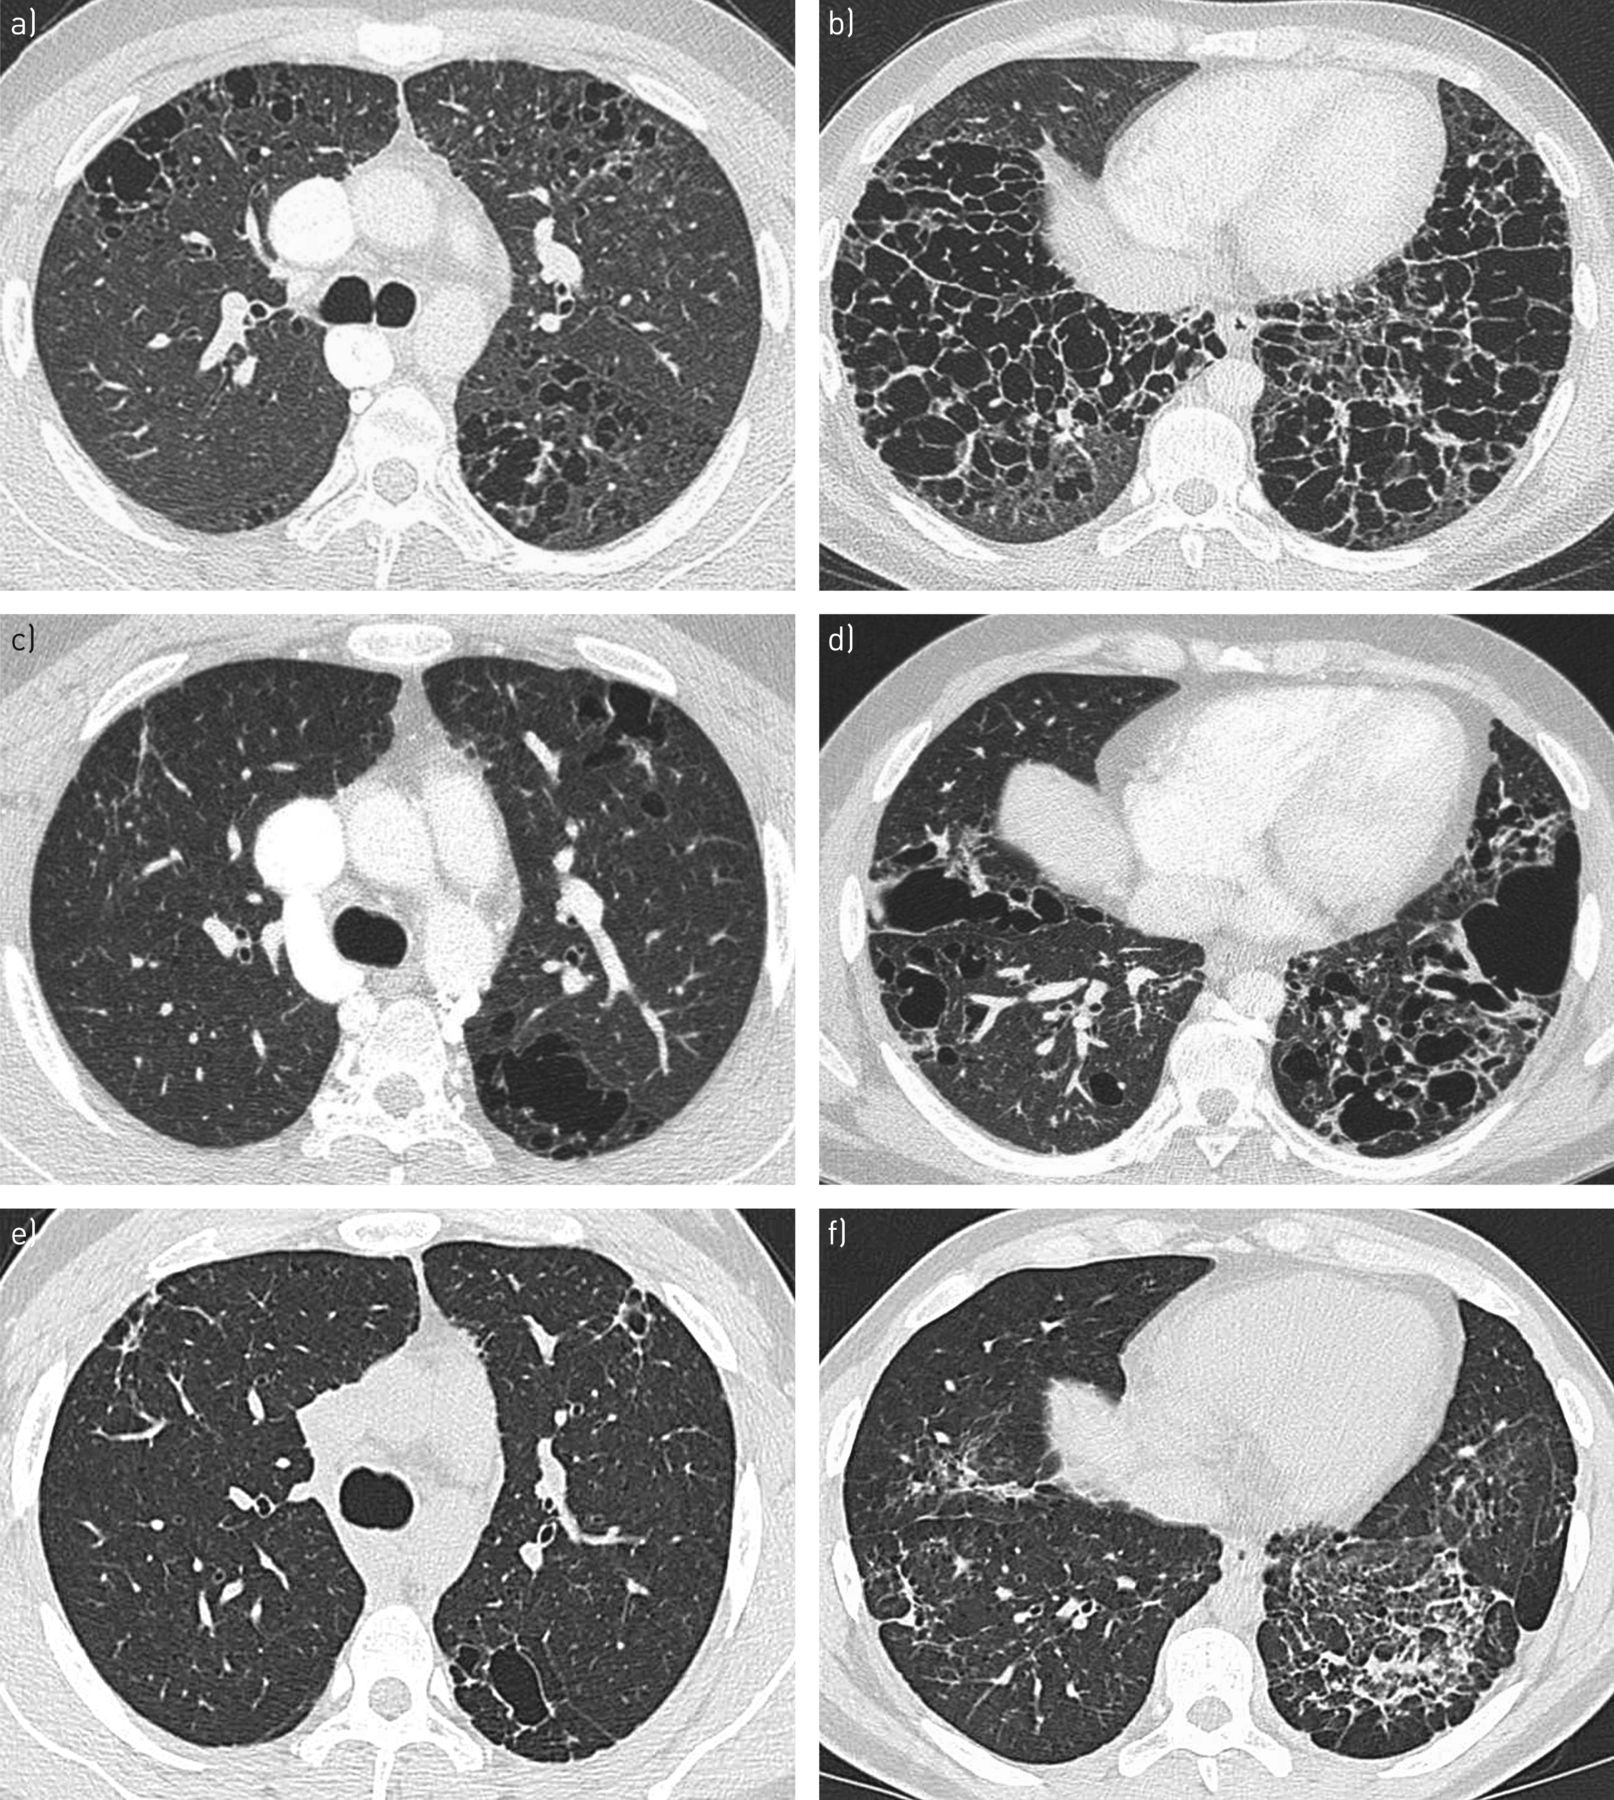

Визуализация и диагностика неинвазивного аспергиллеза с помощью КТ

Раздел: Необычные решения